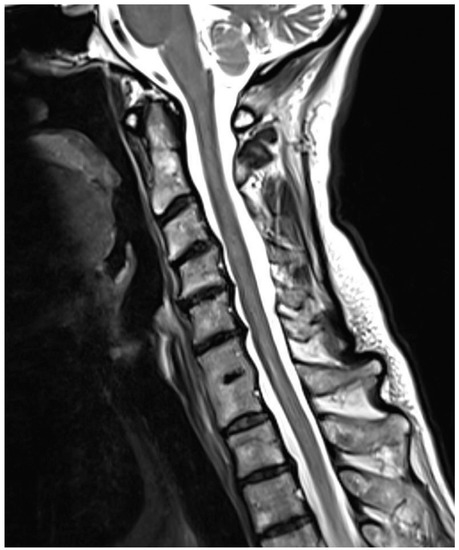

Are Congenital Cervical Block Vertebrae a Risk Factor for Adjacent Segment Disease? A Retrospective Cross-Sectional CT and MR Imaging Study

Adjacent segment disease (ASDI) is a well-described complication of spinal fusion surgery that may ultimately lead to spinal stenosis and repeated surgical intervention. Although congenital block vertebrae also present with degenerative changes in the adjacent segments, this has not yet been systematically investigated. The aim of this study was to assess the presence and degree of ASDI in congenital cervical block vertebrae. Methods: A total of 51 patients with congenital vertebral fusion in one cervical segment were analysed in this IRB-approved retrospective cross-sectional study using available CT/MR imaging. Exclusion criteria were prior spinal surgery and the presence of additional hereditary abnormalities. We assessed the severity of degenerative changes using a sum score. The sum score for adjacent and non-adjacent segments was then divided by the highest possible degeneration score, which resulted in a ratio of severity for adjacent and remaining segments (ranging from 0 to 1). Results: Overall, 35 of 51 patients (68.6%) showed evidence of ASDI, and 34 of 51 patients (66.7%) also showed degenerative changes in the remaining segments. The severity score was significantly higher (p = 0.025) in the segments adjacent to the congenital block vertebrae (mean value 0.307) compared to the non-adjacent segments (mean value 0.188). Conclusions: Our results suggest that ASDI is also caused by congenital block vertebrae of the cervical spine. Full article

Figure 1